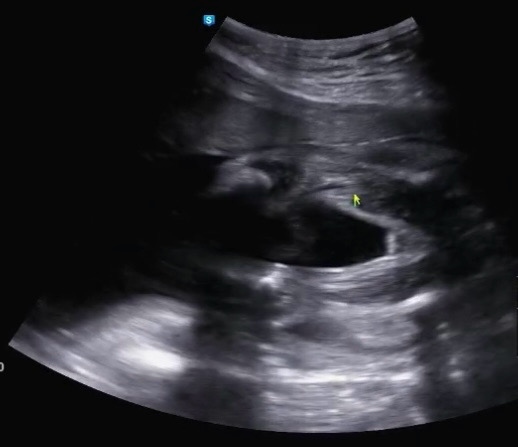

초기에 다니던 병원에서 정밀초음파(20주)때까지 아들확정이었는데 옮긴 병원에서 오늘(23주6일) 본 초음파는 딸처럼 보여요. 현재 병원에서는 성별 안알려주셔서 물어보진 못했는데 어때보이나요?

저는 사진만봐선 딸같네요 밋밋해보여서... 영상으로보면 음경이 보이나요?

각도에 따라 꼬추는 안보여도 고환보이지않나요?